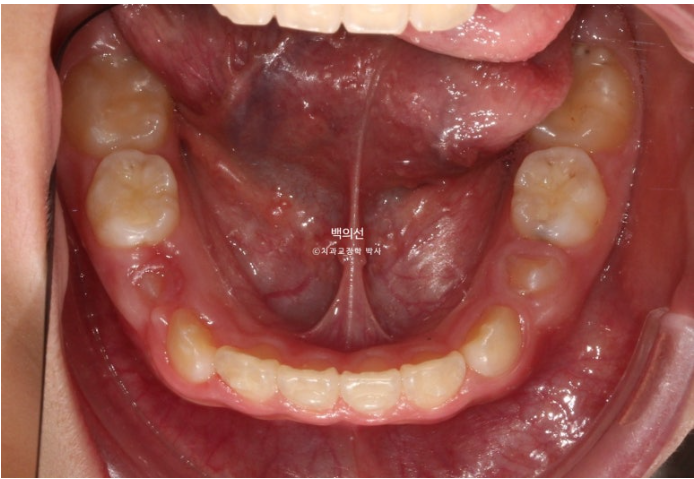

24년 8월까지, 9개월간 첫 세트의 30개 장치를 다 낀 후 모습입니다.

24.08

중심선은 잘 맞게 되었지만,앞니 교합이 절단교합입니다.

한쪽으로 틀어진 턱의 위치가 바로잡히는 과정에서 아래턱이 반대쪽으로 회전을 하면서 소량 앞으로 나오게 되기 때문입니다.

추가장치에서 이 부분은 개선해야 합니다.

영구치들이 올라올 공간은 적절하게 분배가 되었습니다.